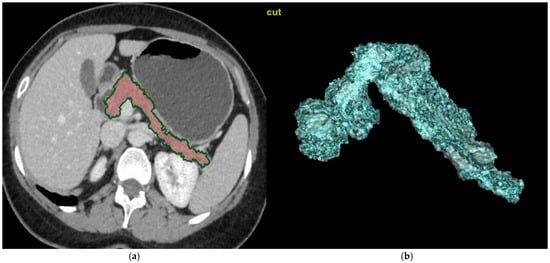

2.3. Image Analysis